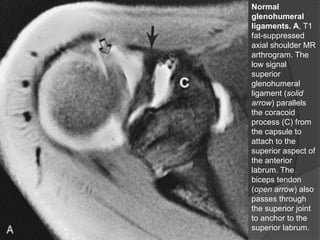

Normal

glenohumeral

ligaments. A, T1

fat-suppressed

axial shoulder MR

arthrogram. The

low signal

superior

ligament (solid

arrow) parallels

the coracoid

process (C) from

the capsule to

attach to the

superior aspect of

the anterior

labrum. The

biceps tendon

(open arrow) also

passes through

the superior joint

to anchor to the

superior labrum.

Normal glenohumeral ligaments. A, T1 fat-suppressed axialshoulder MR arthrogram. The low signal superior glenohumeral ligament (solid arrow) parallels the coracoid process (C) from the capsule to attach to the superior aspect of the anterior labrum. The biceps tendon (open arrow) also passes through the superior joint to anchor to the superior labrum. Dr. Emanuel R. Dantas